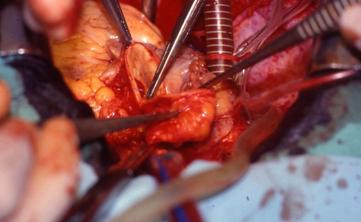

FOTO INTRAOPERATORIA - ANASTOMOSI VASCOLARE

Il tipo di protezione ipotermica ed anossica è sicuro per un tempo di ischemia entro le 4 - 6 ore. A differenza della fase di prelievo la cardioplegia più frequentemente utilizzata durante l'impianto è quella ematica fredda, ripetuta ogni 20 minuti durante il trapianto sul ricevente, alla dose di 600 ml in 3 min. e ad una pressione di 60-80 mm Hg dal bulbo aortico e di 40mmHg in via retrograda. Al termine del confezionamento delle anastomosi e prima del declampaggio aortico viene infusa nel bulbo aortico una soluzione di riperfusione (soluzione cardioplegica ematica normopotassica arricchita di aminoacidi e riscaldata a 36°C ) per reintegrare le scorte energetiche.

La fase di impianto prevede inizialmente l'anastomosi della cuffia atriale sinistra, come per la tecnica di Shumway, mentre le anastomosi successive, eseguite in termino-terminale, sono effettuate in questa successione: vena cava inferiore, vena cava superiore, arteria polmonare, aorta.